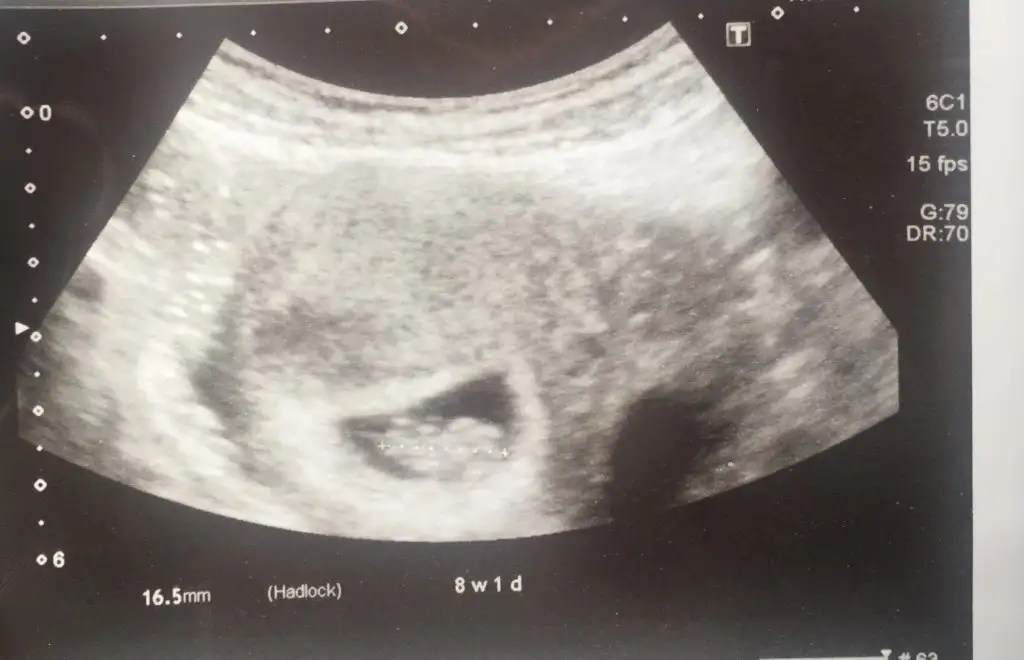

İkiz değil di mi, sanki soldaki de bir kese gibi

Bende 2 kese gordum sanki ya

Ben koyayımburda 8+1 haftalıktık şimdi iseee 8+6 olmuşuz bile